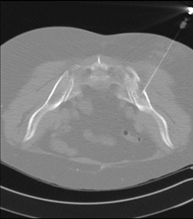

- Sternum CT

Utilising an X-ray system and detectors that rotate around a patient, this radiological scan generates images that are computer-reconstructed to facilitate a close examination of the sternum.

- Clavicle CT

Utilising an X-ray system and detectors that rotate around a patient, this radiological scan generates images that are computer-reconstructed to facilitate a close examination of the clavicles.

- Ribcage CT

Utilising an X-ray system and detectors that rotate around a patient, this radiological scan generates images that are computer-reconstructed to facilitate a close examination of the ribcage.